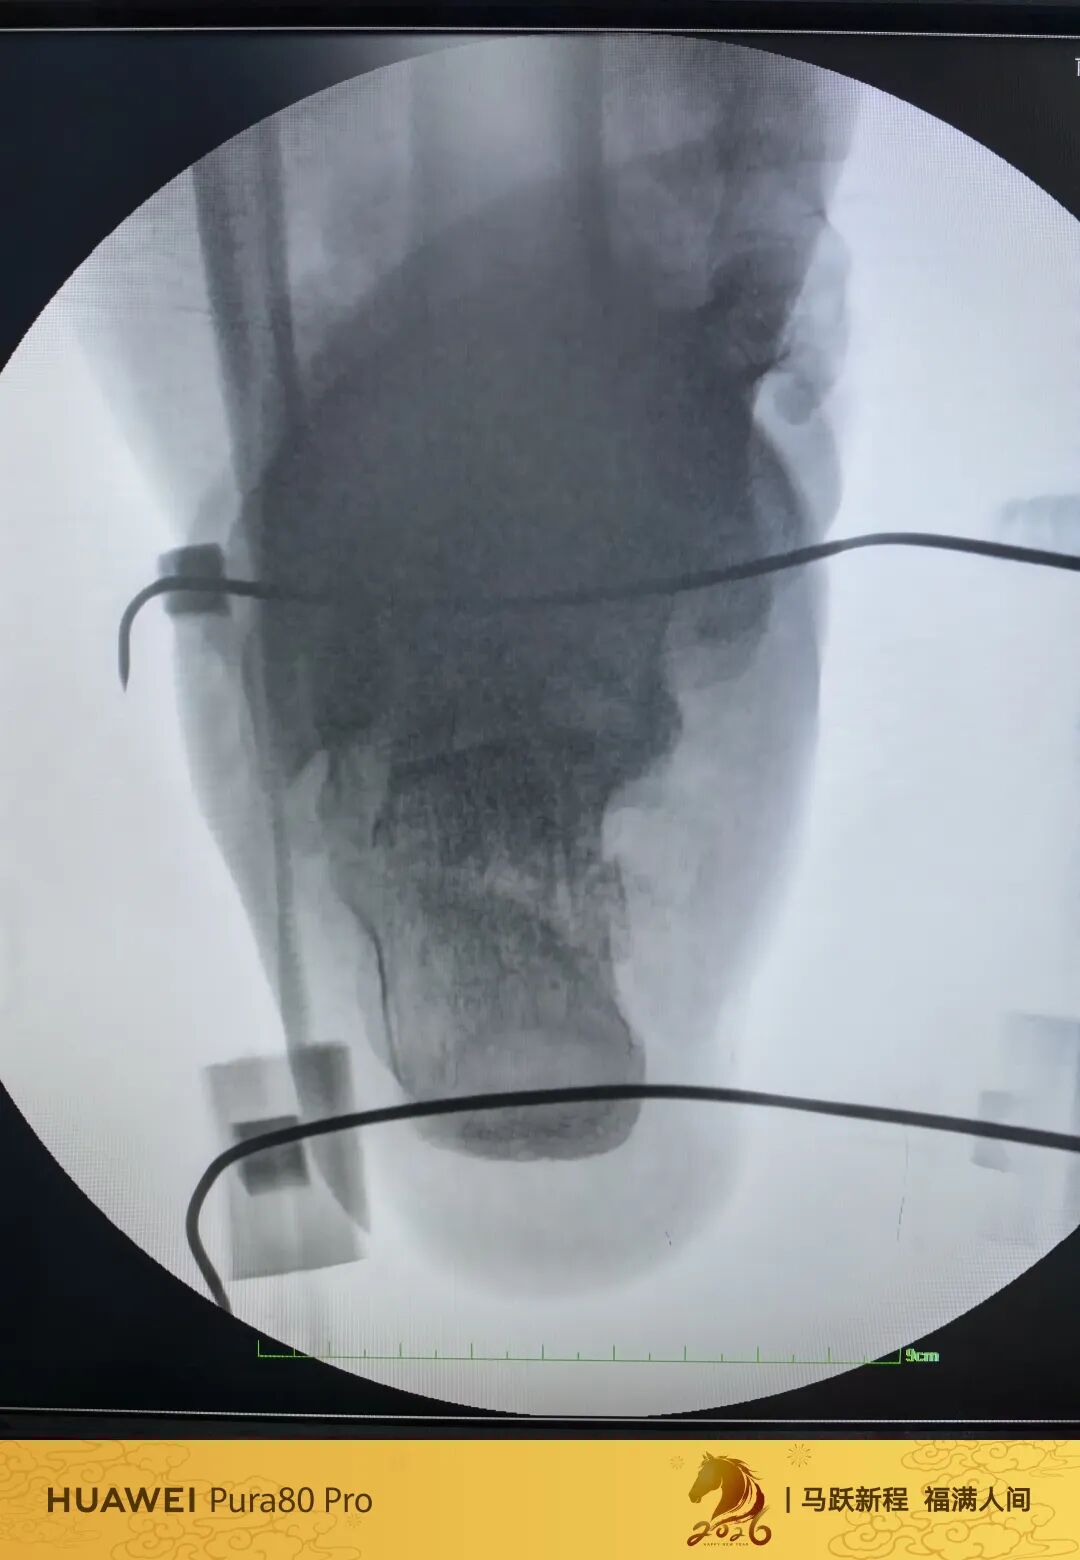

可透视撑开器

高温高压已经消毒10次

低温等离子已经消毒4次

目前来说依旧强硬

强度没问题

高分子材料

质量没得说